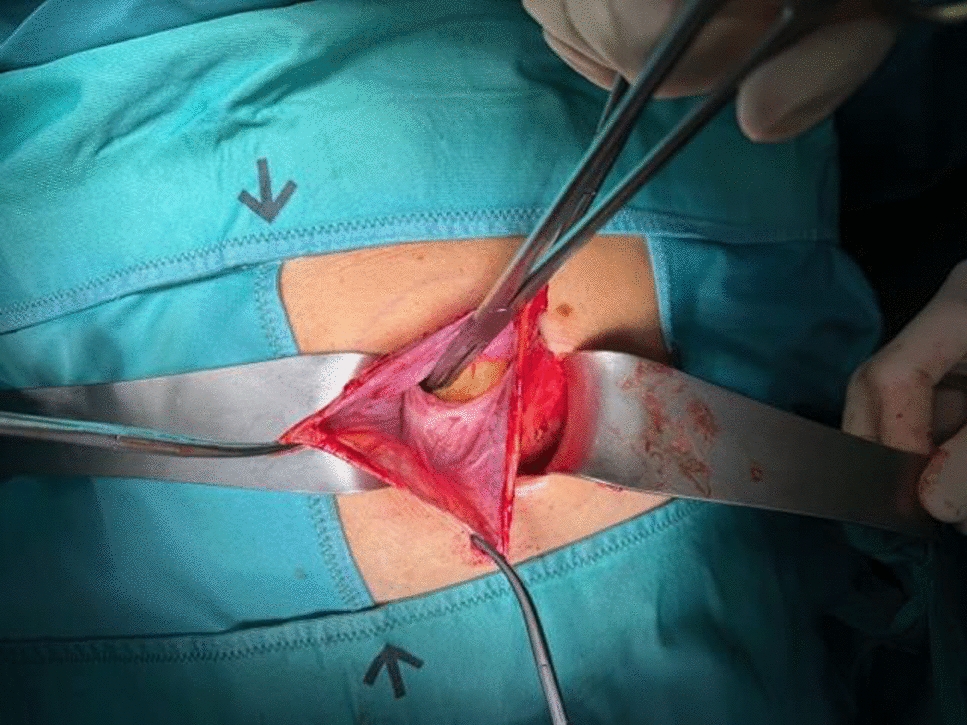

• Figs. 6, 7, 8, 9, 10: intraoperative findings and repair steps with mesh insertion in selected cases

Fig. 6

Selected intraoperative picture with spigelian hernia sac (Foto

© R. Lorenz)

Bild vergrößern

Fig. 7

Fig. 8